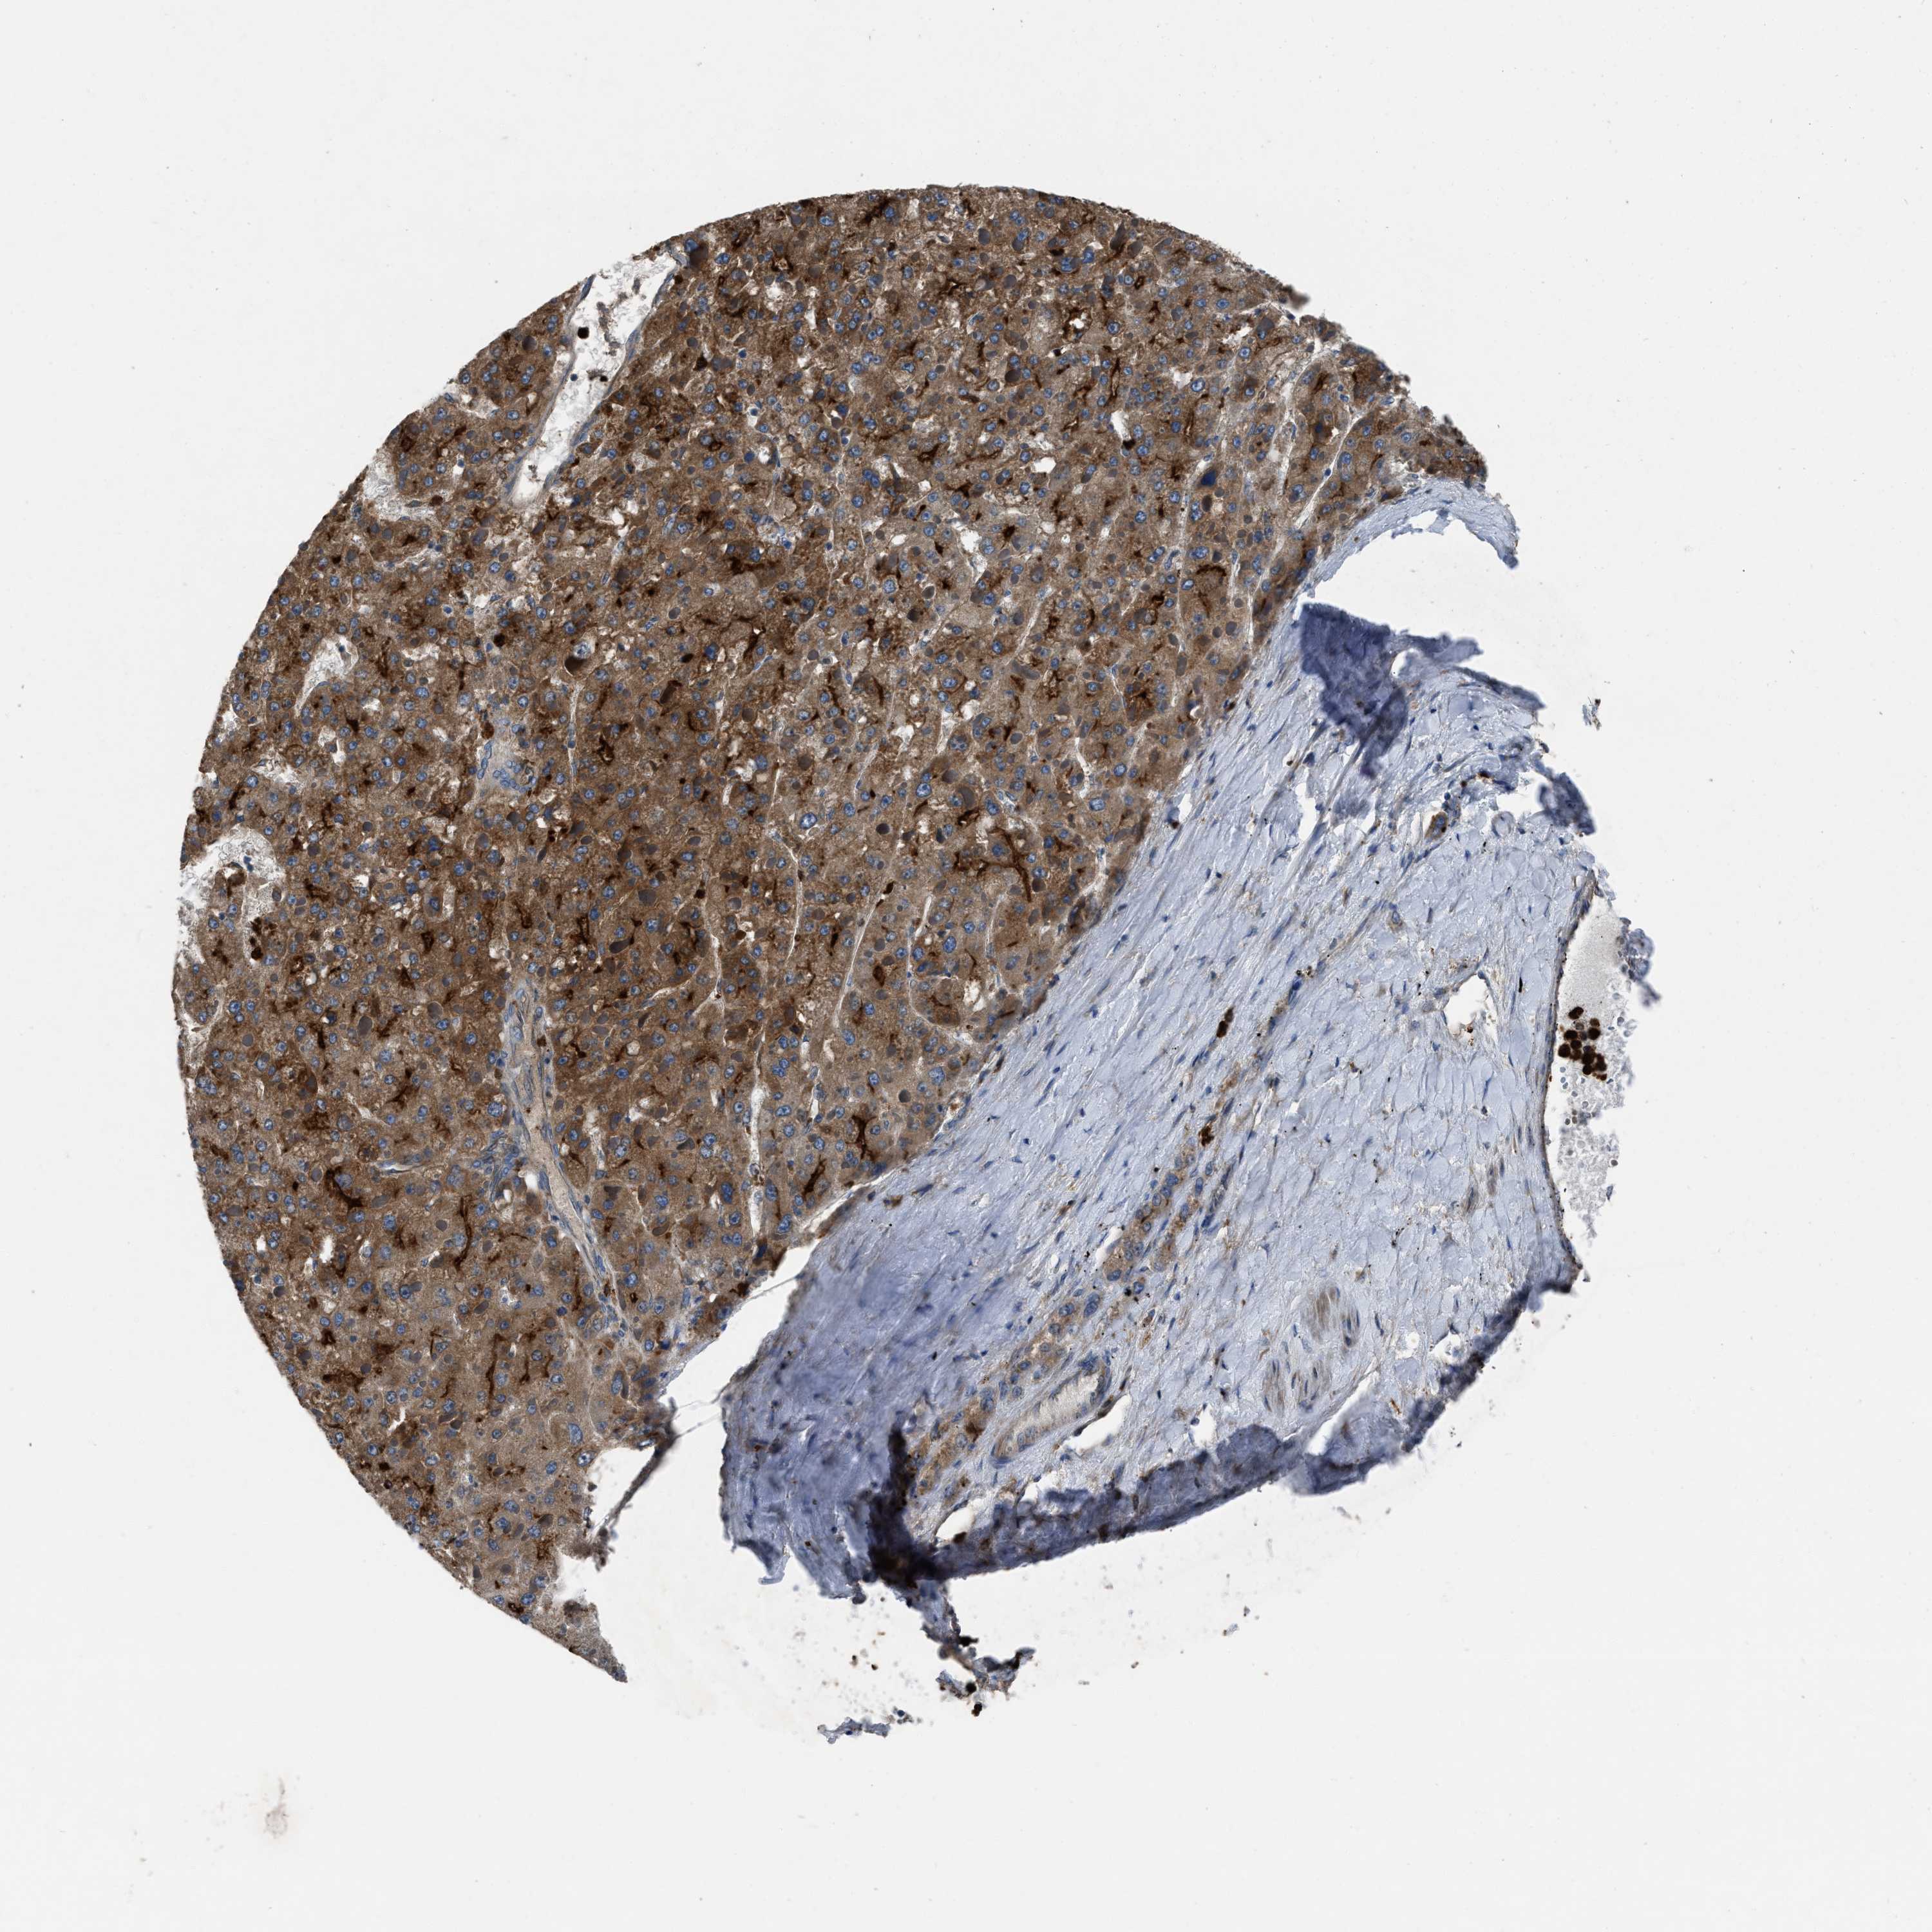

LIVER CANCER - Protein expressioni

A mouse-over function shows sample information and annotation data. Click on an image to view it in a full screen mode. Samples can be filtered based on level of antibody staining by selecting one or several of the following categories: high, medium, low and not detected. The assay and annotation is described here.

Note that samples used for immunohistochemistry by the Human Protein Atlas do not correspond to samples in the TCGA dataset.

Antibody stainingi

Antibody staining in the annotated cell types in the current human tissue is reported as not detected, low, medium, or high, based on conventional immunohistochemistry profiling in selected tissues. This score is based on the combination of the staining intensity and fraction of stained cells.

Each image is clickable and will lead to virtual microscopy that enables deeper exploration of all samples and also displays staining intensity scores, fraction scores and subcellular localization as well as patient and tissue information for each sample.

Antibody HPA018793

Antibody HPA018816

Antibody CAB017815

Staining

High

Medium

Low

Not detected

Intensity

Strong

Moderate

Weak

Negative

Quantity

>75%

75%-25%

<25%

None

Location

Nuclear

Cytoplasmic/membranous

Cytoplasmic/membranous,nuclear

Carcinoma, Hepatocellular, NOS

Cholangiocarcinoma